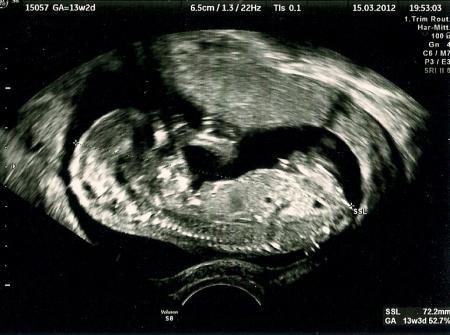

Das freut mich sehr für Dich! Ich war gestern auch sehr stolz, als ich beim Arzt den Wurm zappeln gesehn habe. Bei 13+2 mit 7,2 cm. Aber leider wollte der Zwerg sich noch nicht outen..Wieder 4 Wochen warten. LG

Bild zu